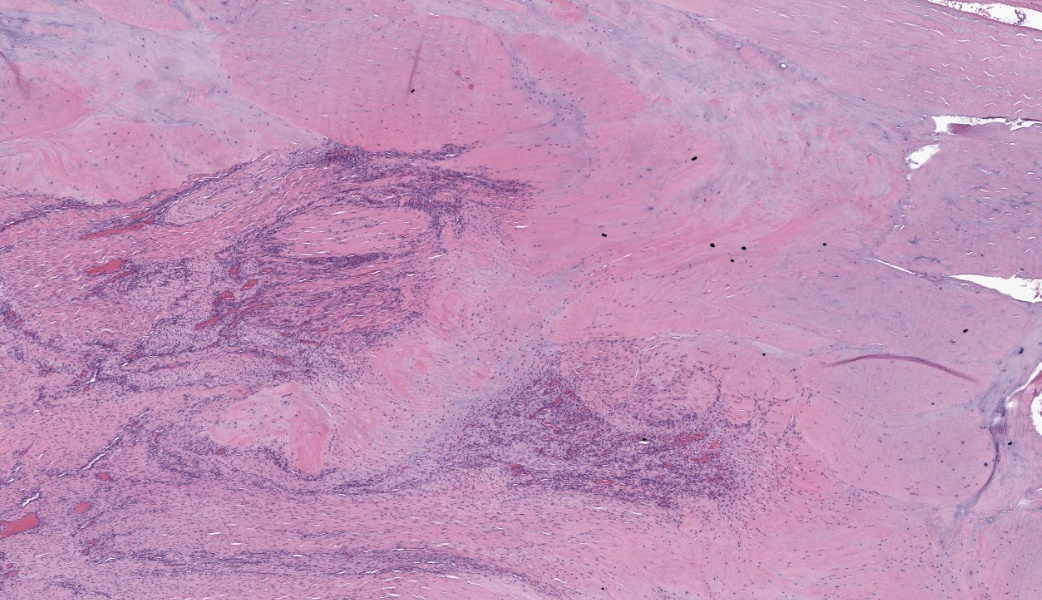

Suspensory ligament, right rear branch. Compared to a branch of the clinically normal right front suspensory ligament, collagen fibers are irregular and often form intersecting or divergent bundles. In many areas, there are fewer fibroblasts among collagen fibers than in the normal control. Throughout the tissue, wavy tendrils of pale basophilic, Alcian blue-positive matrix dissect between collagen bundles. Similar material surrounds increased numbers of variably sized, dilated and tortuous blood vessels. These vessels have thin walls and are lined by plump endothelial cells, and are often surrounded by loosely arranged stellate cells. In other areas, there is chondroid metaplasia, with clustered and individual chondrocyte-like cells in lacunae surrounded by amorphous, pale basophilic matrix, which is sometimes faintly mineralized. There is rare hemorrhage.Contributor's Morphologic Diagnoses:

The terms degenerative suspensory ligament desmitis (DSLD) and suspensory ligament degeneration (SLD) are used somewhat synonymously, with DSLD often used to describe horses with a clinical diagnosis of suspensory ligament degeneration, and SLD used to describe histologic findings in the suspensory ligaments of horses that may or may not have a clinical diagnosis of DSLD. DSLD causes chronic, progressive multi-limb lameness of variable severity, often recognized by enlarged, hyperextended or dropped fetlocks.8 The rear limbs are typically more affected.3,8 In addition, the terms suspensory ligament desmitis or suspensory ligament desmopathy may be used to describe any of a variety of clinically or ultrasonographically detected injuries anywhere along the length of the suspensory ligament.3 Histology is rarely performed in these cases, especially in the acute phase, and it is unclear if these injuries are related to degenerative changes.3Histologic changes in SLD/DSLD include loss of longitudinal arrangement of collagen fibers, proteoglycan accumulation, presence of chondrocytes, hemorrhage, vascular proliferation, and widened interstitial connective tissue septa.4,6 Despite the use of the term desmitis, inflammatory cells are not present.4 These changes are reported to be more severe in the branches of the suspensory ligament than in the body or origin of the ligament.3,5

The major histologic findings within ligaments suffering from SLD include loss of longitudinal arrangement of collagen fibers (disorganization), proteoglycan accumulation (increased ground substance), presence of chondrocytes (chondroid metaplasia), hemorrhage, vascular proliferation, widened interstitial connective tissue septae, and a lack of inflammatory cells.8 As this disease develops, regardless of cause, degenerating collagen fascicles blend together and there is either death of the tenocytes/ligamentocytes or metaplasia of tenocytes/ligamentocytes into chondrocytes. Fibrosis develops within and around the ligament and is usually associated with hypertrophied tenocytes/ligamentocytes. These areas are generally interpreted as failed attempts at repair.

As these changes progress, the suspensory ligament (SL) progressively thickens, weakens, and ultimately ruptures, resulting in the classic dropped fetlocks seen in affected horses.8,9 Some horses may also have neurogenic muscular atrophy secondary to either nerve entrapment within areas of fibrosis or due to nerve compression from a thickened and enlarged SL. SLD is typically more evident in the pelvic limbs and is usually bilateral, although some horses have all four limbs affected.3,8,9